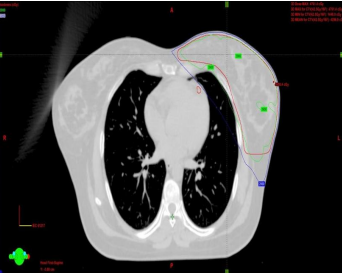

e) Radiotherapy planning

The treatment plan was carried out using a CT-based, Intensity-modulated Radiotherapy or 3-dimensional conformal radiotherapy. According to the patient’s comfortable breathing pattern, planning was done either on FB or DIBH. Beam angle modification, collimator leaf adjustment, and planning optimization are utilized to minimize LAD and heart dose. Plan evaluation was done and if satisfactory Quality assurance was done and transferred for treatment execution.

Figure 3a, Figure 3b

Figure 3: a) LAD CONTOURED AND SPARED, b) LAD CONTOURED BUT NOT SPARED

Heart and LAD dose-volume-histogram (DVH) data from both groups (ARM A, ARM B) were compared. (figure 4)

Figure 4a (Graph 1: DVH of one Retrospective patient), Figure 4b (Graph 2: DVH of one Prospective patient)